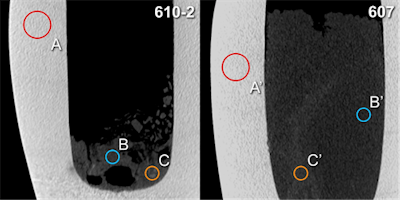

The thickness and high density of the calcite mineral of the canopic jars limited x-ray image contrast. CT scans showed few artifacts and revealed hyperdense structures of organ-specific morphology, surrounded by a hypodense homogeneous material. CT scans revealed all the jars were partially filled with material of mostly heterogeneous density (mean 208 Hounsfield units [HU]).

In one jar (jar 607), structures of distinct longitudinal morphology and higher density (mean 344 HU, range from 71 HU to 595 HU) were clearly distinguishable from a homogeneous surrounding material of lower density (mean 186 HU, range from -88 HU to 448 HU).